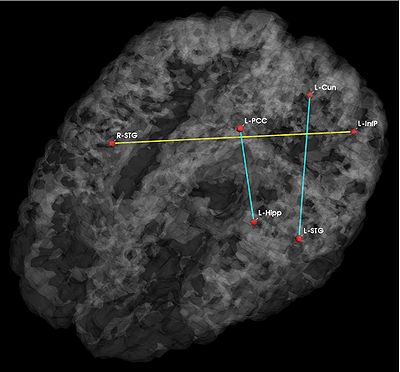

Fig 1. Significant anatomical and functional connectivity differences. Blue lines indicate higher connectivity in the control group; yellow lines indicate higher connectivity in the schizophrenia population.

Fig. 1 depicts the significantly different anatomical and functional connections identified by the algorithm. As seen, schizophrenia patients exhibit increased functional connectivity between the parietal/posterior cingulate region and the frontal lobe and reduced functional connectivity between the parietal/posterior cingulate region and the temporal lobe. These results confirm the hypotheses of widespread functional connectivity changes in schizophrenia and of functional abnormalities involving the default network.

The differences in anatomical connectivity implicate the superior temporal gyrus and hippocampus. We note that relatively few anatomical connections exhibit significant differences between the two populations. This may stem from our choice of ROIs. In particular, we rely on Freesurfer parcellations, which provide anatomically meaningful correspondences across subjects and mitigate the effects of minor registration errors. However, they may be too big to capture structural differences between the groups. We emphasize that our model can be easily applied to finer scale parcelations in future studies.